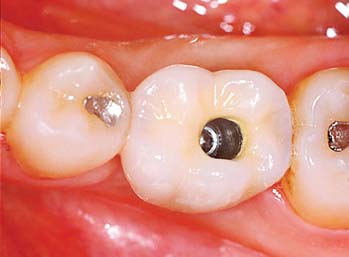

Several systems have been developed to comply with these demands. Common indications include congenitally missing maxillary lateral incisors (Fig. 13-42) and teeth in which endodontic treatment was unsuccessful (Fig. 13-43). Screw loosening has most commonly been associated with the terminally positioned single molar implant crown (Fig. 13-44).

Fig. 13-43 A, Occlusal view of a single tooth implant crown replacing a fractured mandibular premolar. B, Implant crown with screw access restored.